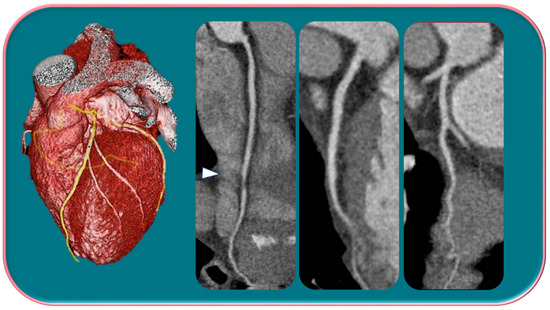

Kim et al. [29] in a study evaluated gender differences regarding the distribution and prevalence of CAC, its relationship to clinical risk factors, and the effect of a high calcium score (≥100) on subsequent initiation of medical therapy by evaluating a court of 542 individuals, of whom 279 were female and 263 were male. The data demonstrated an increasing CAC score with age, regardless of sex. However, women showed significantly lower CAC scores than men in the same age group. The lower CAC scores in women are likely in part indicative of the fact that women have a greater amount of non-calcifying plaque, so-called low-attenuation plaque, than men, indicating that lower CAC scores may actually be related to higher-risk plaque. However, there are also cases, although less frequent, of men with low-attenuation atheromasic plaque (Figure 1). Another interesting finding emerged from the correlation between CAC and clinical risk factors: for both sexes, age had a similar effect on CAC score (OR 1.11 and 1.12, respectively); however, in men, obesity showed a significant effect on CAC score (OR 2.16), while in women, smoking showed a significant effect on CAC score (OR 4.27). This result clearly demonstrated that the traditional clinical risk factors and which women, therefore, share with men actually have different clinical impact in the two genders. Finally, it was investigated how the CAC score result affected the further management of men vs. women with a CAC score ≥100 when adjusted for concurrent coronary CTA findings (moderate to severe lesions vs. non-obstructive lesions) in initiating aspirin and statin therapy [29].

Figure 1.

Male, 39-years-old, patients with history of dyslipidemia, type-1 obesity, and higher level of stress at work. The patient reported a non-anginal chest pain for which an ergometric ECG stress test was performed, and the results were negative. According to the Diamond–Forrester score, the patient was first categorized as a low pre-test probability risk of having CAD. To correctly rule-out CAD, the patients underwent CCTA examination, which showed a severe non-calcific plaque in the distal right coronary artery (white arrowhead).

Kim et al. [29], moreover, reported that, while, for patients with moderate-severe stenosis (>50%) found at CTA, no gender difference was observed in initiation of therapy, strong differences were shown in patients with non-obstructive atherosclerotic lesions. Aspirin and statin use increased in both sexes but men with non-obstructive coronary artery disease (NOCAD) were significantly more likely to take preventive medications than women. In particular, among men with NOCAD, 68.2% were on aspirin and 86.4% were on statin after the CTA, which is a significant increase from 18.2% and 36.4% before the test, respectively. In contrast, among women with non-obstructive lesions, only 27.3% were on aspirin and 45.5% on statin after the test, compared to 18.2% each before the test [29].